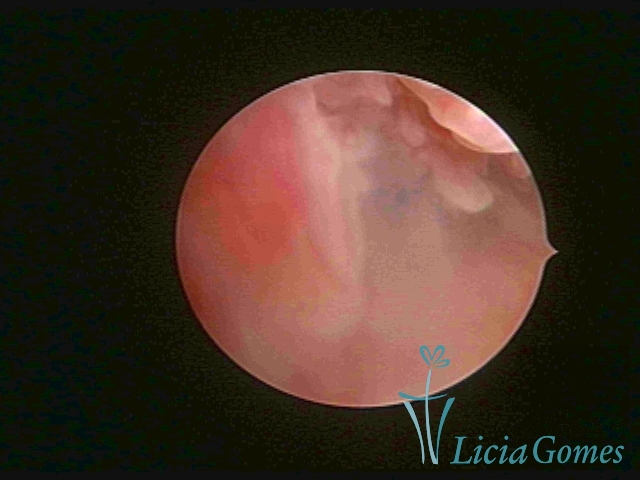

Terceira porção ou porção superior

Apresenta a mucosa com a superfície lisa e pouco vascularizada até a altura do orifício interno